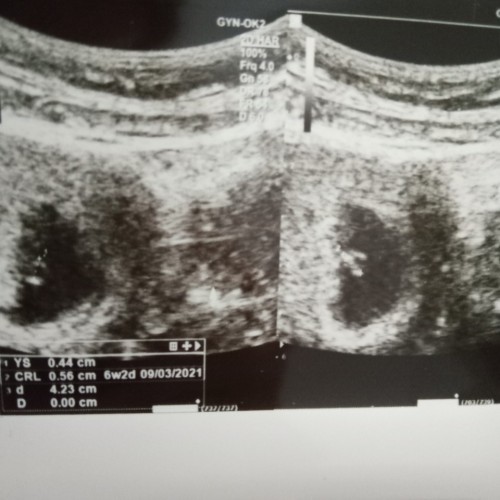

6w sy segini bun, ada kantung kehamilan, janin sm yolksac

Saya dulu 5w juga kayak gitu bun. Masih kantung aja. 7w baru keliatan janinnya, itu jg kecil bgt.

Beda2 bun.. aku dlu udah keliatan buletan kecil gitu pas 5w 4d Tar 7w keatas baru keliatan babynya